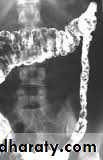

* Loss of normal feathery appearance of the small bowel

* Flocculation & segmentation of the Ba

* Widening of the spaces between bowel loops due to mucosal edema

*+/_ spiky appearance of the small bowel loops